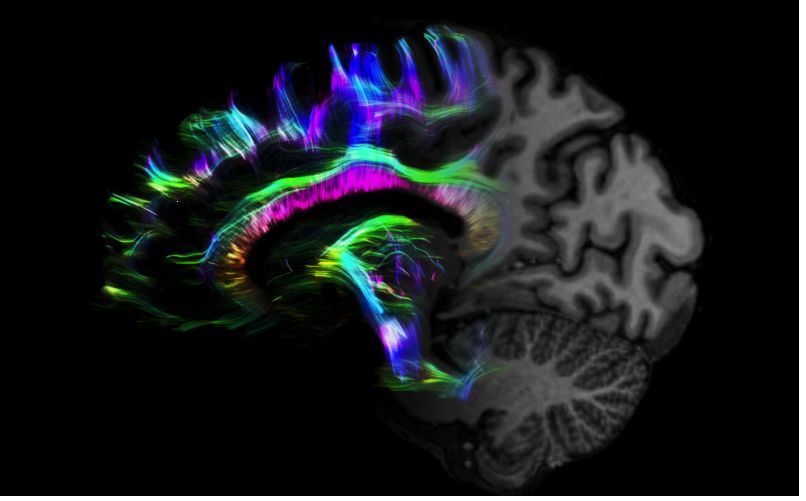

1毫米的各向同性分辨率DTI:神經纖維束的交叉細節(jié)顯示